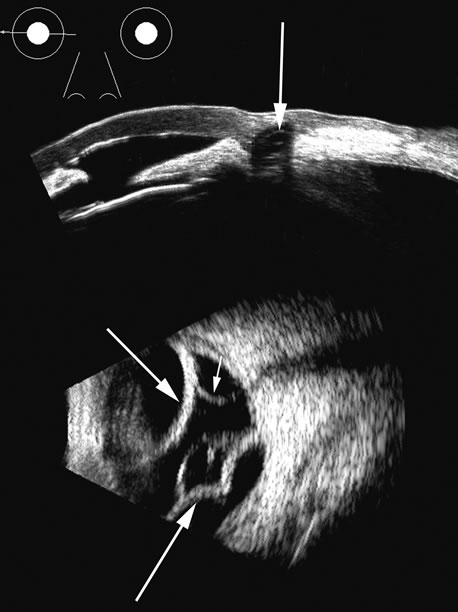

The choroid, like the retina, is highly reflective and may resemble the retina when detached. Its thickness, which includes the retina, Bruch's membrane, and the choriocapillaris (tunica ruyschiana) is not usually differentiable when measured with routine ultrasound;12 however, it may be measured with digital techniques.18 Anatomically, the choroidal elevation is usually a smoothly round, convex surface, limited posteriorly by the vortex veins and anteriorly at any point up to the base of the iris (Fig. 17). The choroidal space should be examined for echoes (blood) or a clear zone, as seen with effusion or the serous part of a hemorrhage. In evaluating membranes from retina or choroid, it is always helpful to repeat the examinations at a later time.

Fig. 17. This patient with a Molteno tube was treated for glaucoma. The top 50 MHz B-scan clearly shows the Molteno Tube (arrow). The bottom 10 MHz B-scan of the same patient demonstrates a choroidal detachment (large arrow) with associated posterior retinal detachment (small arrow). Choroidal elevations are typically convex, highly reflective surfaces with posterior limitation at the vortex vessels. Retina will always attach at the optic nerve. Choroidal elevations are often noted in several quadrants, as seen here.